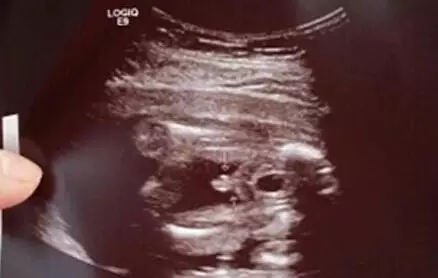

2017生男生女计算器

这个是网上一位妈妈晒得女女的B超图片,可以看到图片中在中间很明显木有小鸡鸡,是一位女宝宝的部位。